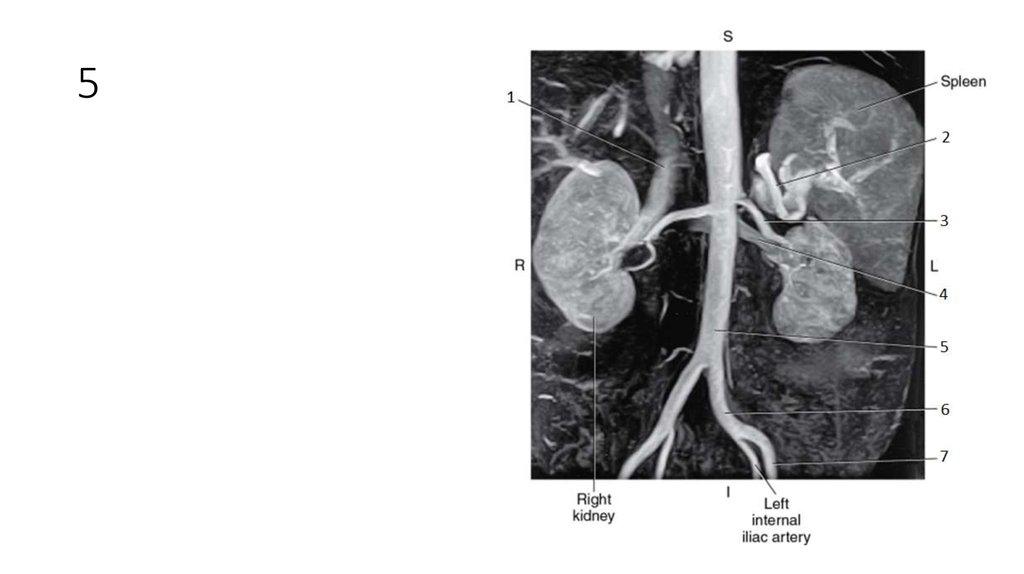

62. 1

63. 1

• Inferior Vena Cava (IVC)

64. 2

65. 2

• Splenic Artery

66. 3

67. 3

• Left Renal Artery

68. 4

69. 4

• Left Renal Vein

70. 5

71. 5

• Aorta

72. 6

73. 6

• Left Common Iliac Artery

74. 7

75. 7

• Left External Iliac Artery